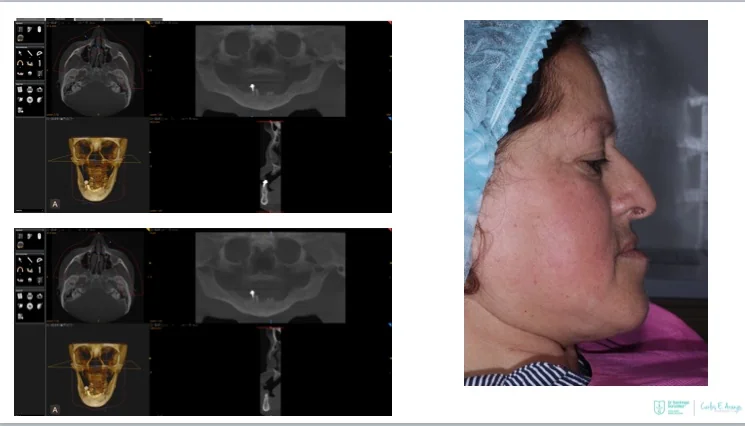

Two straight anterior implants and two implants tilted up to 45º in the posterior - Immediate Function (fixed provisional bridge)

For patients meeting criteria for immediate loading of implants - Graftless Procedure: Bone grafting is avoided by tilting the posterior implants, utilizing available bone.